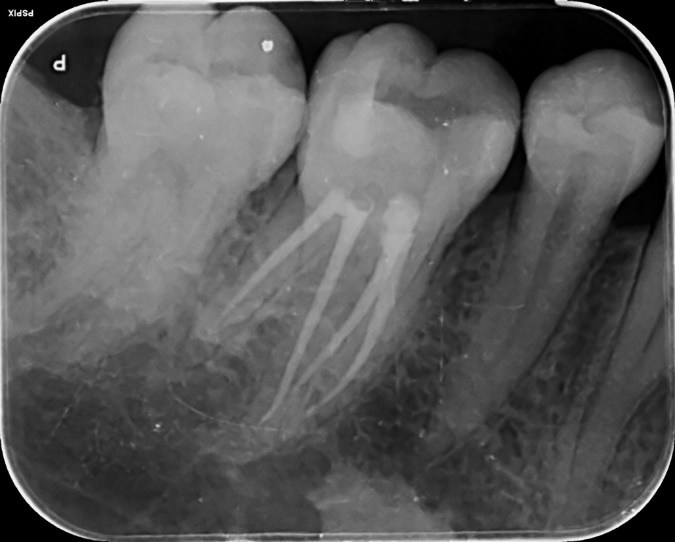

Lower Molar Primary root canal treatment